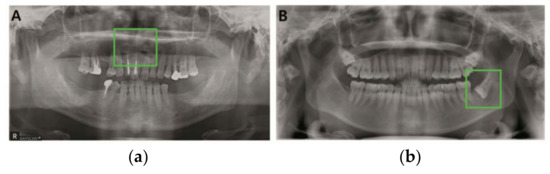

Mandibular fracture is one of the most frequent injuries in oral and maxillo-facial surgery. Radiologists diagnose mandibular fractures using panoramic radiography and cone-beam computed tomography (CBCT). Panoramic radiography is a conventional imaging modality, which is less complicated than CBCT. This paper proposes the [...] Read more.

Mandibular fracture is one of the most frequent injuries in oral and maxillo-facial surgery. Radiologists diagnose mandibular fractures using panoramic radiography and cone-beam computed tomography (CBCT). Panoramic radiography is a conventional imaging modality, which is less complicated than CBCT. This paper proposes the diagnosis method of mandibular fractures in a panoramic radiograph based on a deep learning system without the intervention of radiologists. The deep learning system used has a one-stage detection called you only look once (YOLO). To improve detection accuracy, panoramic radiographs as input images are augmented using gamma modulation, multi-bounding boxes, single-scale luminance adaptation transform, and multi-scale luminance adaptation transform methods. Our results showed better detection performance than the conventional method using YOLO-based deep learning. Hence, it will be helpful for radiologists to double-check the diagnosis of mandibular fractures. Full article

Show Figures